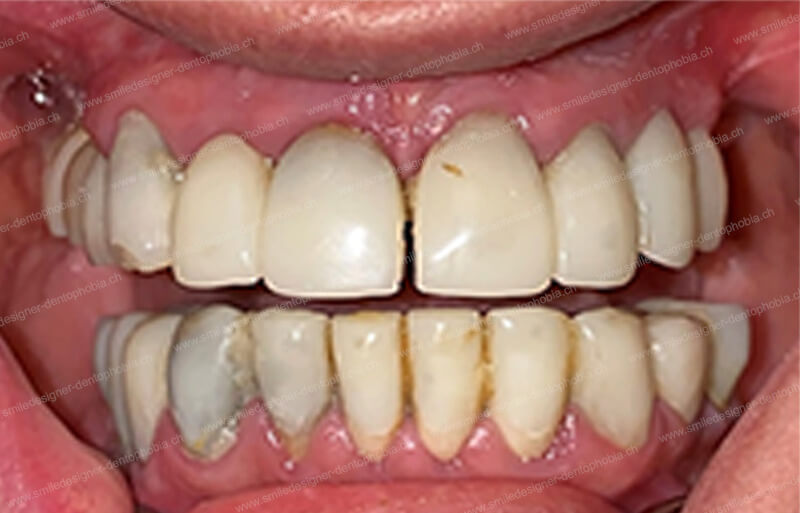

Cas clinique « GOLD DAMAGE CONTROL MCI » maxillaire : Bridge implanto-porté avec extensions postérieures (ALL ON 8). Version définitive des bridges avec un cosmétique en céramique.

- Esthétique et fonction restaurées : les prothèses reproduisent le festonnage gingival naturel et offrent une occlusion parfaite, protégeant les articulations temporo-mandibulaires (ATM).